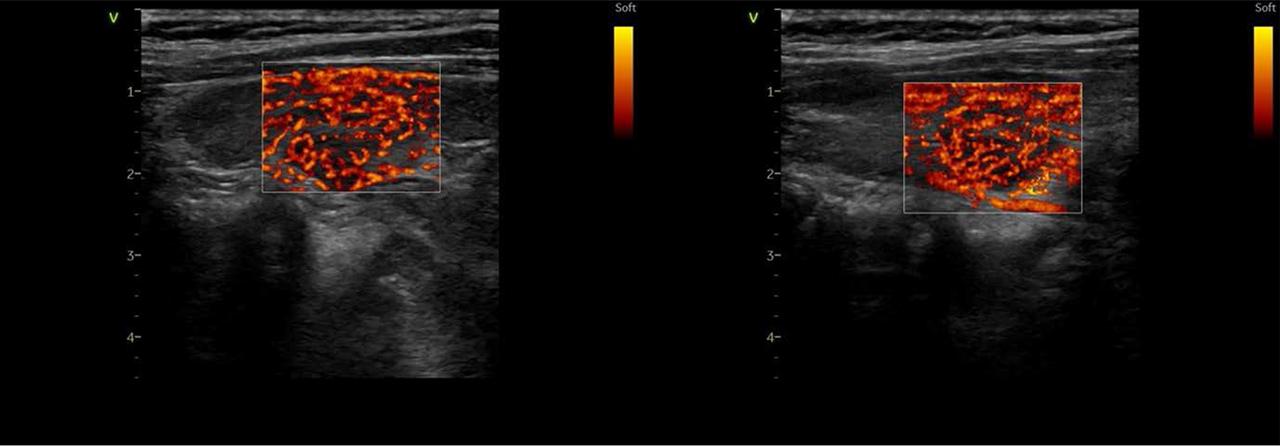

To assess the appearance of the thyroid gland, a thyroid ultrasound was performed. The results indicated an enlarged thyroid with slightly increased thyroid vascularity (Figure 3).

Vascularization of the left and right thyroid lobe